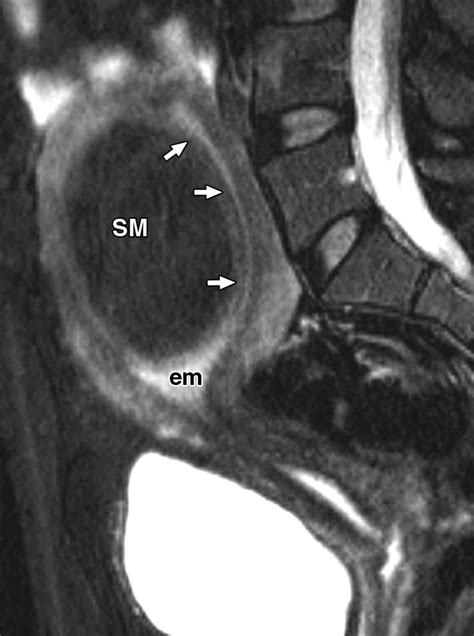

• Submucosal fibroids: These grow just underneath the lining of the uterus and can protrude into the uterine cavity.

• MRI: Magnetic resonance imaging provides detailed images of the uterus and can help determine the exact size and location of fibroids.